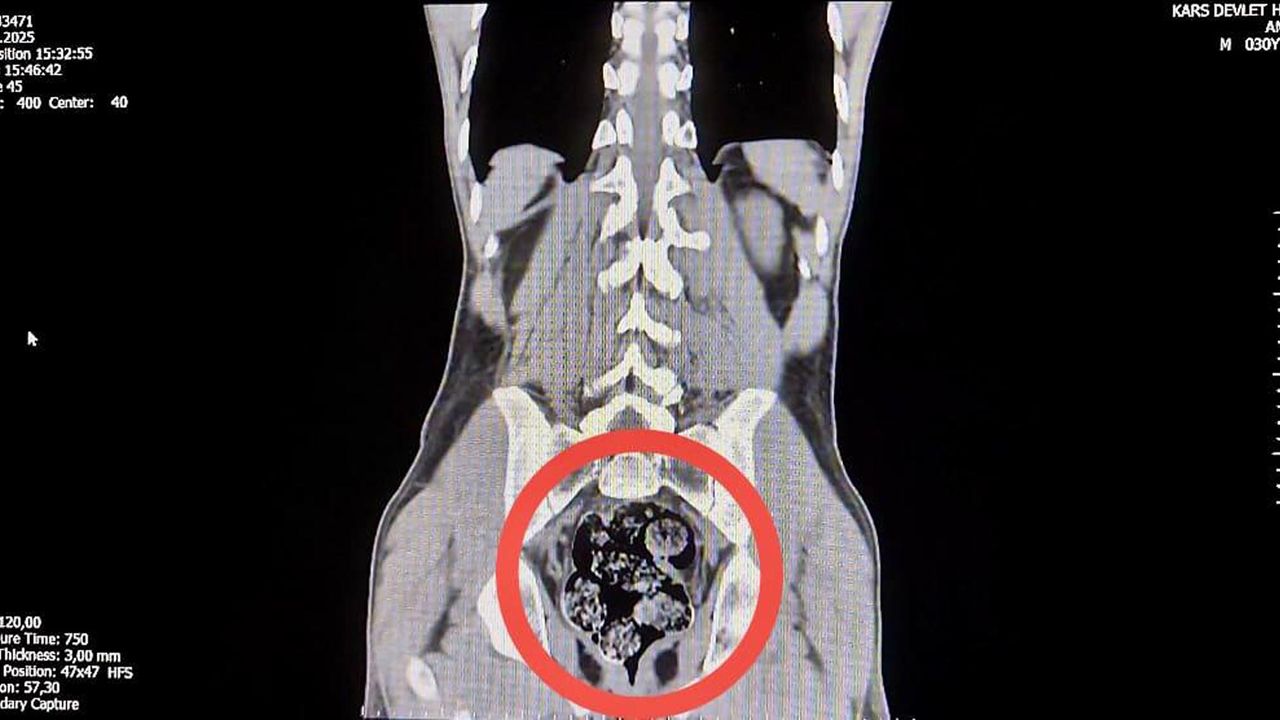

Kars Emniyet Müdürlüğü Narkotik Suçlarla Mücadele Şube Müdürlüğü ekipleri, Digor-Kars kara yolunda yaptığı uygulamada, Iğdır'dan gelen yolcu otobüsünde arama yaptı. Polis, hareketlerinden şüphelendiği İran uyruklu Jafar Ayrem (42) ve Amır Rafıeı Shekarbaghanı (34) gözaltına aldı. Kars Harakani Devlet Hastanesi'ne götürülen şüphelilerden Shekarbaghanı'nin çekilen röntgeninde, makatında uyuşturucu tespit edildi. 7 parça halinde 203,02 gram metamfetamin, hastanede cerrahi operasyonla çıkarıldı. Emniyetteki işlemlerinin ardından adliyeye sevk edilen şüpheliler, çıkarıldığı hakimlikçe tutuklandı. (DHA)